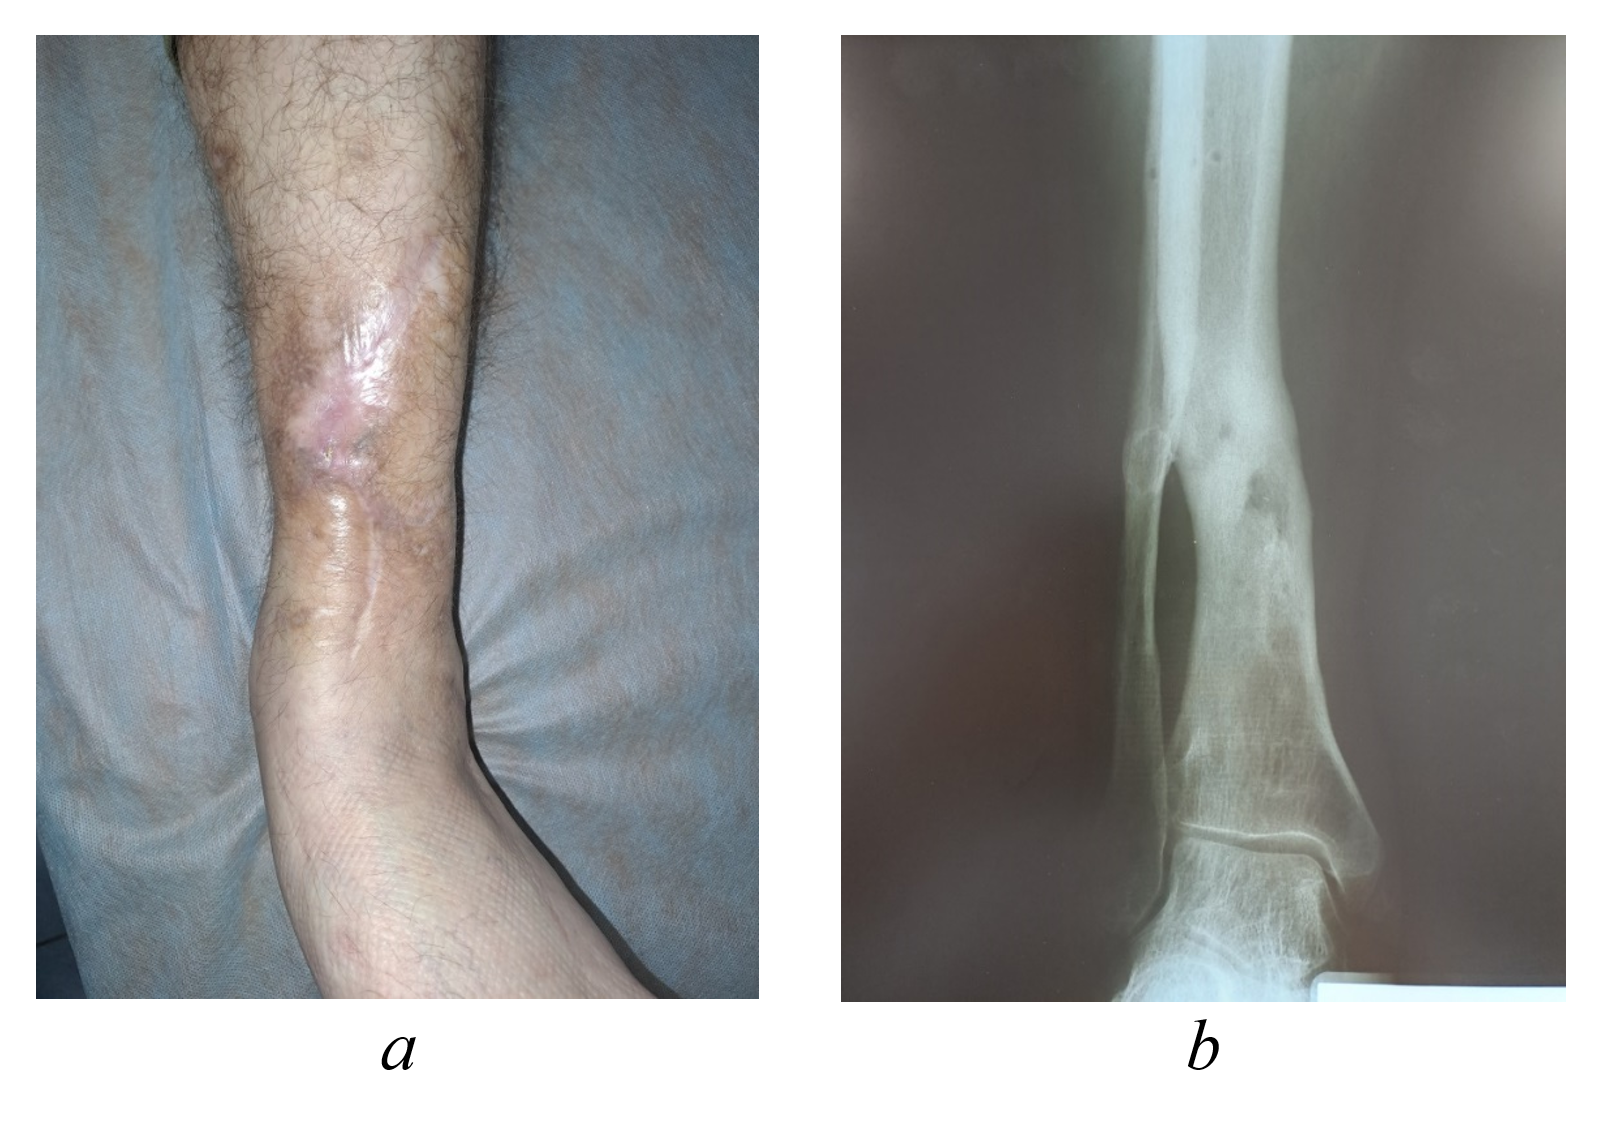

Figure 6 - Clinical appearance (a) and radiographic findings (b) of the left shin in patient Yu., 43 years old, at 7-month postoperative follow-up

Figure 7 - Clinical appearance (a) and radiographic imaging (b) of the left shin in patient Yu., 43 years old, at 13-month postoperative follow-up